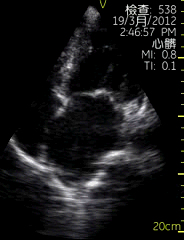

心尖四腔切面

| 图像名称: | 心尖四腔切面(二维) |

| 心尖四腔切面(二维) |

| 心尖四腔切面(彩色) | | 介绍重点: | 心脏各腔室大小正常、瓣膜运动协调; |

| 左房增大,二尖瓣启闭受限; |

| 左房增大,二尖瓣舒张期前向血流速度增快,收缩期可见蓝色反向血流; | | 临床用途: | 评估心脏各腔室大小,瓣膜结构与功能;(正常图像) |

| 风湿性心脏病:二尖瓣狭窄伴关闭不全; |